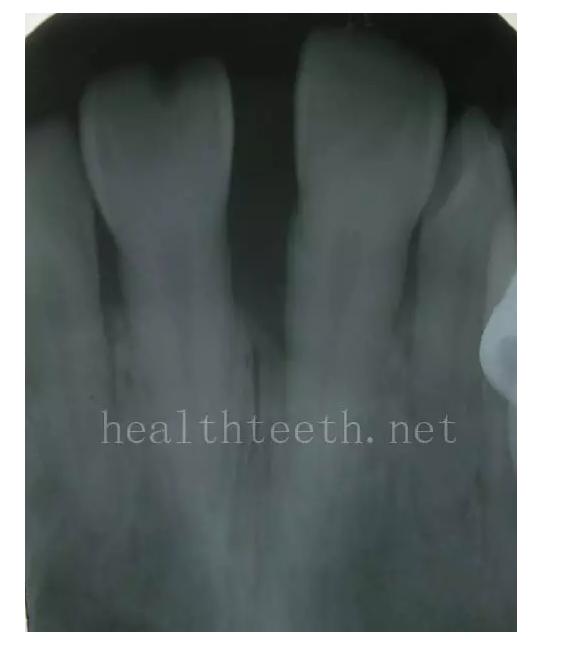

牙片顯示牙槽骨的垂直吸收